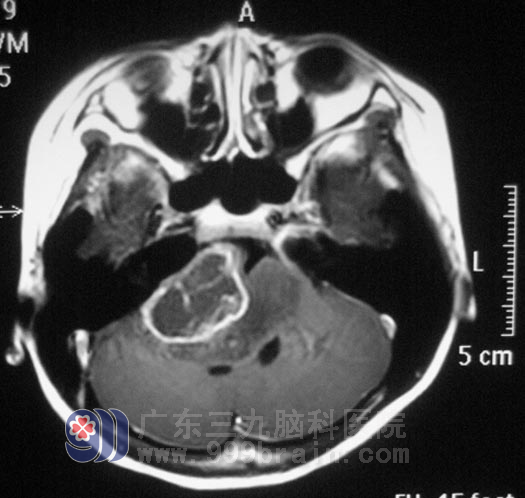

在广东三九脑科医院综合神经外科,鲁明主任给妮妮做了详细的体查:双眼向左水平震颤,右眼外展受限,右眼右视露白约5mm,右眼闭合不全,左侧鼻唇沟变浅,伸舌左偏,右耳听力明显下降。初步诊断为:脑干病变。头颅MR检查提示右侧脑干异常信号影,大小约51.8mm×39.7mm×41.9mm,增强后有部分强化,脑干明显肿胀,以桥脑、中脑及右侧桥臂为著。完善相关检查后,由鲁明主任主刀,在全麻下行脑干右侧、右侧桥小脑角区肿瘤切除术,术中显微镜下见肿瘤呈白色,质软,血供一般,边界尚清,面听神经横跨肿瘤,肿瘤下界于后组神经粘连,肿瘤内侧与椎动脉、脑干粘连紧密,在显微镜下仔细分离,面听神经及后组神经保留完整。http://www.999brain.com/

▲手术前